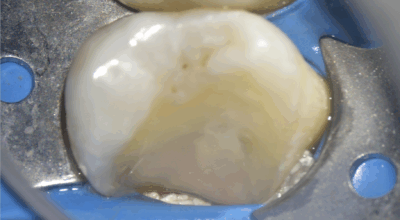

Cas clinique d’une 17 (2e molaire en haut à droite)

Coiffage pulpaire indirect : 96,4% de taux de succès